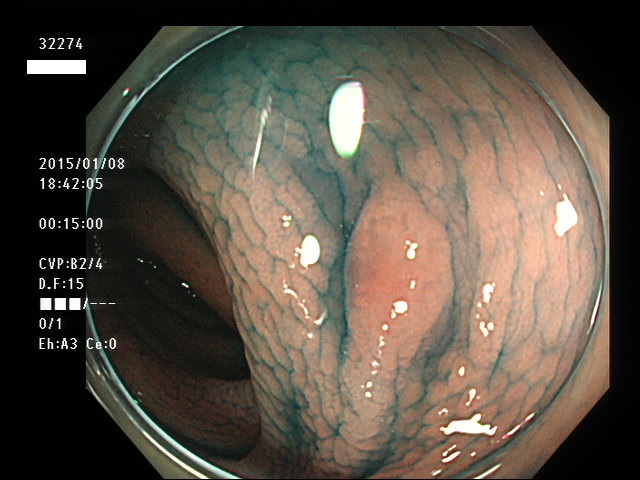

上記100名より抽出した平坦・陥凹型腺腫(=癌化の危険が高いが見落としやすい病変)の内視鏡写真